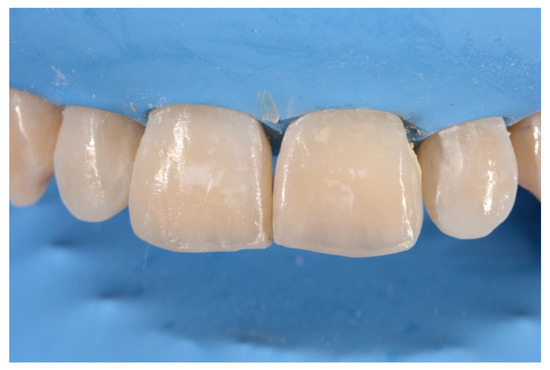

2. Case Presentation

- Layering free-hand buccal surface.